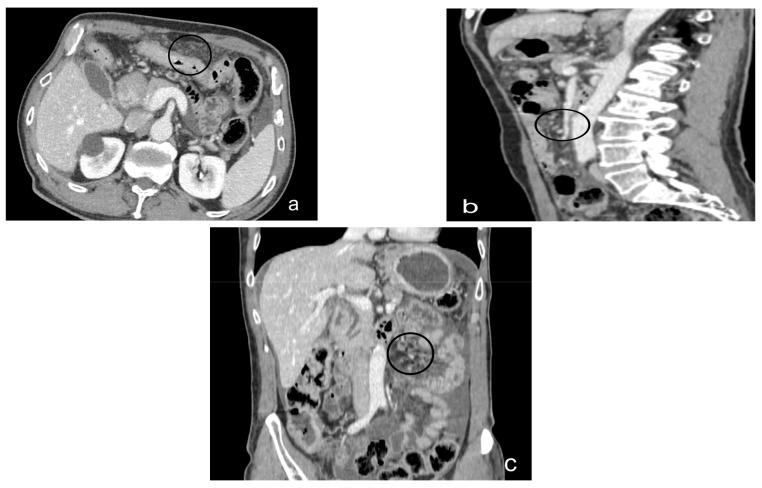

Peritoneal carcinosis is a condition characterized by the spread of cancer cells to the peritoneum, which is the thin membrane that lines the abdominal cavity. It is a serious condition that can result from many different types of cancer, including ovarian, colon, stomach, pancreatic, and appendix cancer. The diagnosis and quantification of lesions in peritoneal carcinosis are critical in the management of patients with the condition, and imaging plays a central role in this process. Radiologists play a vital role in the multidisciplinary management of patients with peritoneal carcinosis. They need to have a thorough understanding of the pathophysiology of the condition, the underlying neoplasms, and the typical imaging findings. In addition, they need to be aware of the differential diagnoses and the advantages and disadvantages of the various imaging methods available. Imaging plays a central role in the diagnosis and quantification of lesions, and radiologists play a critical role in this process. Ultrasound, computed tomography, magnetic resonance, and PET/CT scans are used to diagnose peritoneal carcinosis. Each imaging procedure has advantages and disadvantages, and particular imaging techniques are recommended based on patient conditions. Our aim is to provide knowledge to radiologists regarding appropriate techniques, imaging findings, differential diagnoses, and treatment options. With the advent of AI in oncology, the future of precision medicine appears promising, and the interconnection between structured reporting and AI is likely to improve diagnostic accuracy and treatment outcomes for patients with peritoneal carcinosis.

腹膜癌是一种以癌细胞扩散至腹膜为特征的病症,腹膜是衬于腹腔的一层薄膜。它是一种严重的病症,可由多种不同类型的癌症引发,包括卵巢癌、结肠癌、胃癌、胰腺癌和阑尾癌。腹膜癌中病变的诊断和定量对于该病症患者的管理至关重要,而影像学在这一过程中发挥着核心作用。放射科医生在腹膜癌患者的多学科管理中起着至关重要的作用。他们需要对该病症的病理生理学、潜在肿瘤以及典型的影像学表现有透彻的了解。此外,他们需要知晓鉴别诊断以及各种可用影像学方法的优缺点。影像学在病变的诊断和定量中起着核心作用,放射科医生在这一过程中起着关键作用。超声、计算机断层扫描、磁共振成像和正电子发射断层显像/计算机断层扫描(PET/CT)用于诊断腹膜癌。每种成像检查都有其优缺点,会根据患者情况推荐特定的成像技术。我们的目的是向放射科医生提供有关合适技术、影像学表现、鉴别诊断和治疗方案的知识。随着人工智能在肿瘤学中的出现,精准医学的未来似乎很有前景,结构化报告与人工智能之间的相互联系可能会提高腹膜癌患者的诊断准确性和治疗效果。